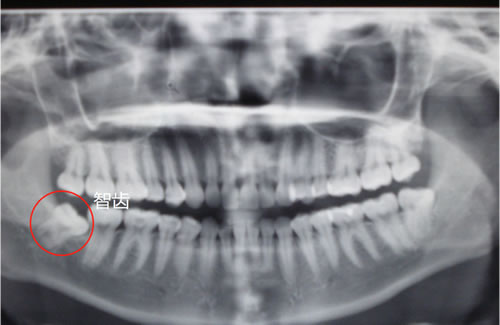

3不正常生长的智齿是什么样?

不正常生长的智齿有:横着的,斜向前的,斜向后的等等奇形怪状都有。

如下图:

不知道怎么长的智齿